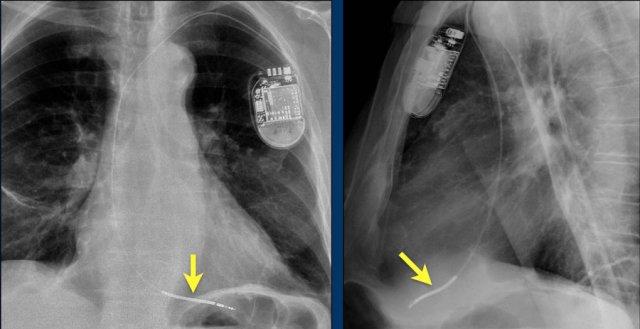

Bệnh nhân này đã được sửa chữa ba van:

- Van hai lá

- Van ba lá

- Van động mạch chủ

Có máy tạo nhịp tim với điện cực thượng tâm mạc.

Phương án này được lựa chọn vì người ta cho rằng điện cực đặt theo đường thông thường vào thất phải sẽ ảnh hưởng quá nhiều đến chức năng của van ba lá nhân tạo.

Mũi tên trắng chỉ vào van động mạch chủ.

Mũi tên vàng chỉ vào van hai lá.